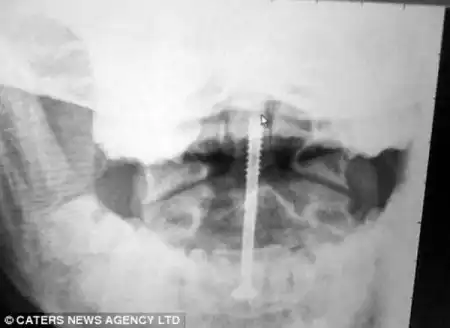

Груда искореженного металла вот все, что осталось от машины. Трудно поверить, но девушка-видитель выжила и это еще не все. В результате ДТП позвоночник девушки был значительно разрушен, не оставалось другого выбора и девушке вживили металические импланты. Теперь она действительно Железная Леди.